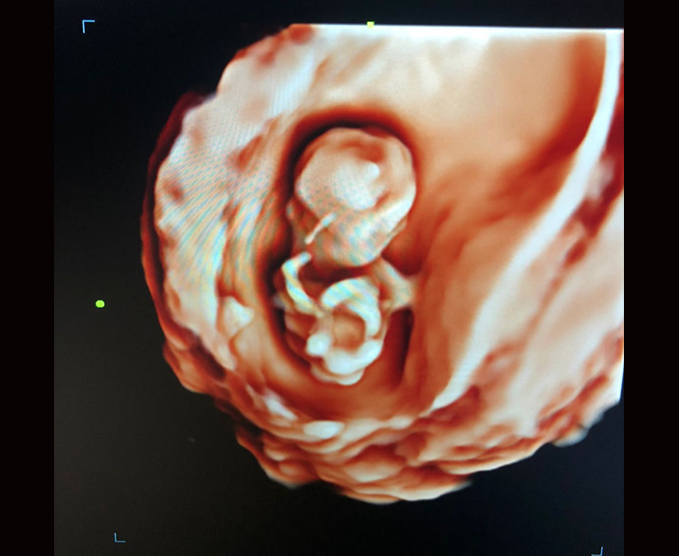

El ultrasonido obstétrico utiliza ondas sonoras para producir imágenes de un bebé (embrión o feto) que está dentro de una mujer embarazada, como así también del útero y los ovarios de la madre. No utiliza radiación ionizante, no tiene efectos nocivos conocidos, y es el método preferido para la vigilancia de las mujeres embarazadas y sus bebés que aún no han nacido.